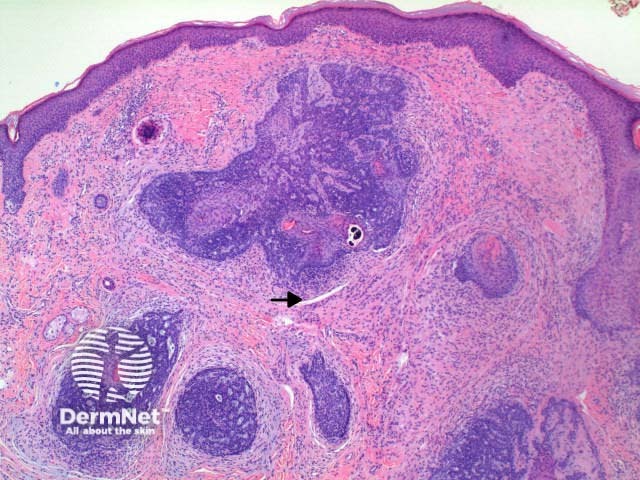

Scanning power view reveals a tumour comprised of multiple nodules situated within the dermis (Figure 1). Small horn cysts, abortive hair follicles and calcification are frequently seen (Figure 2). The stroma is denser and more cellular than with basal cell carcinoma, and there is often focal stromal cracking (Figure 2, arrow). Often pronounced bulbar differentiation may be seen, emulating the follicular bulb and papilla; these structures have been referred to as papillary mesenchymal bodies. (Figure 3, arrow).

Figure 1